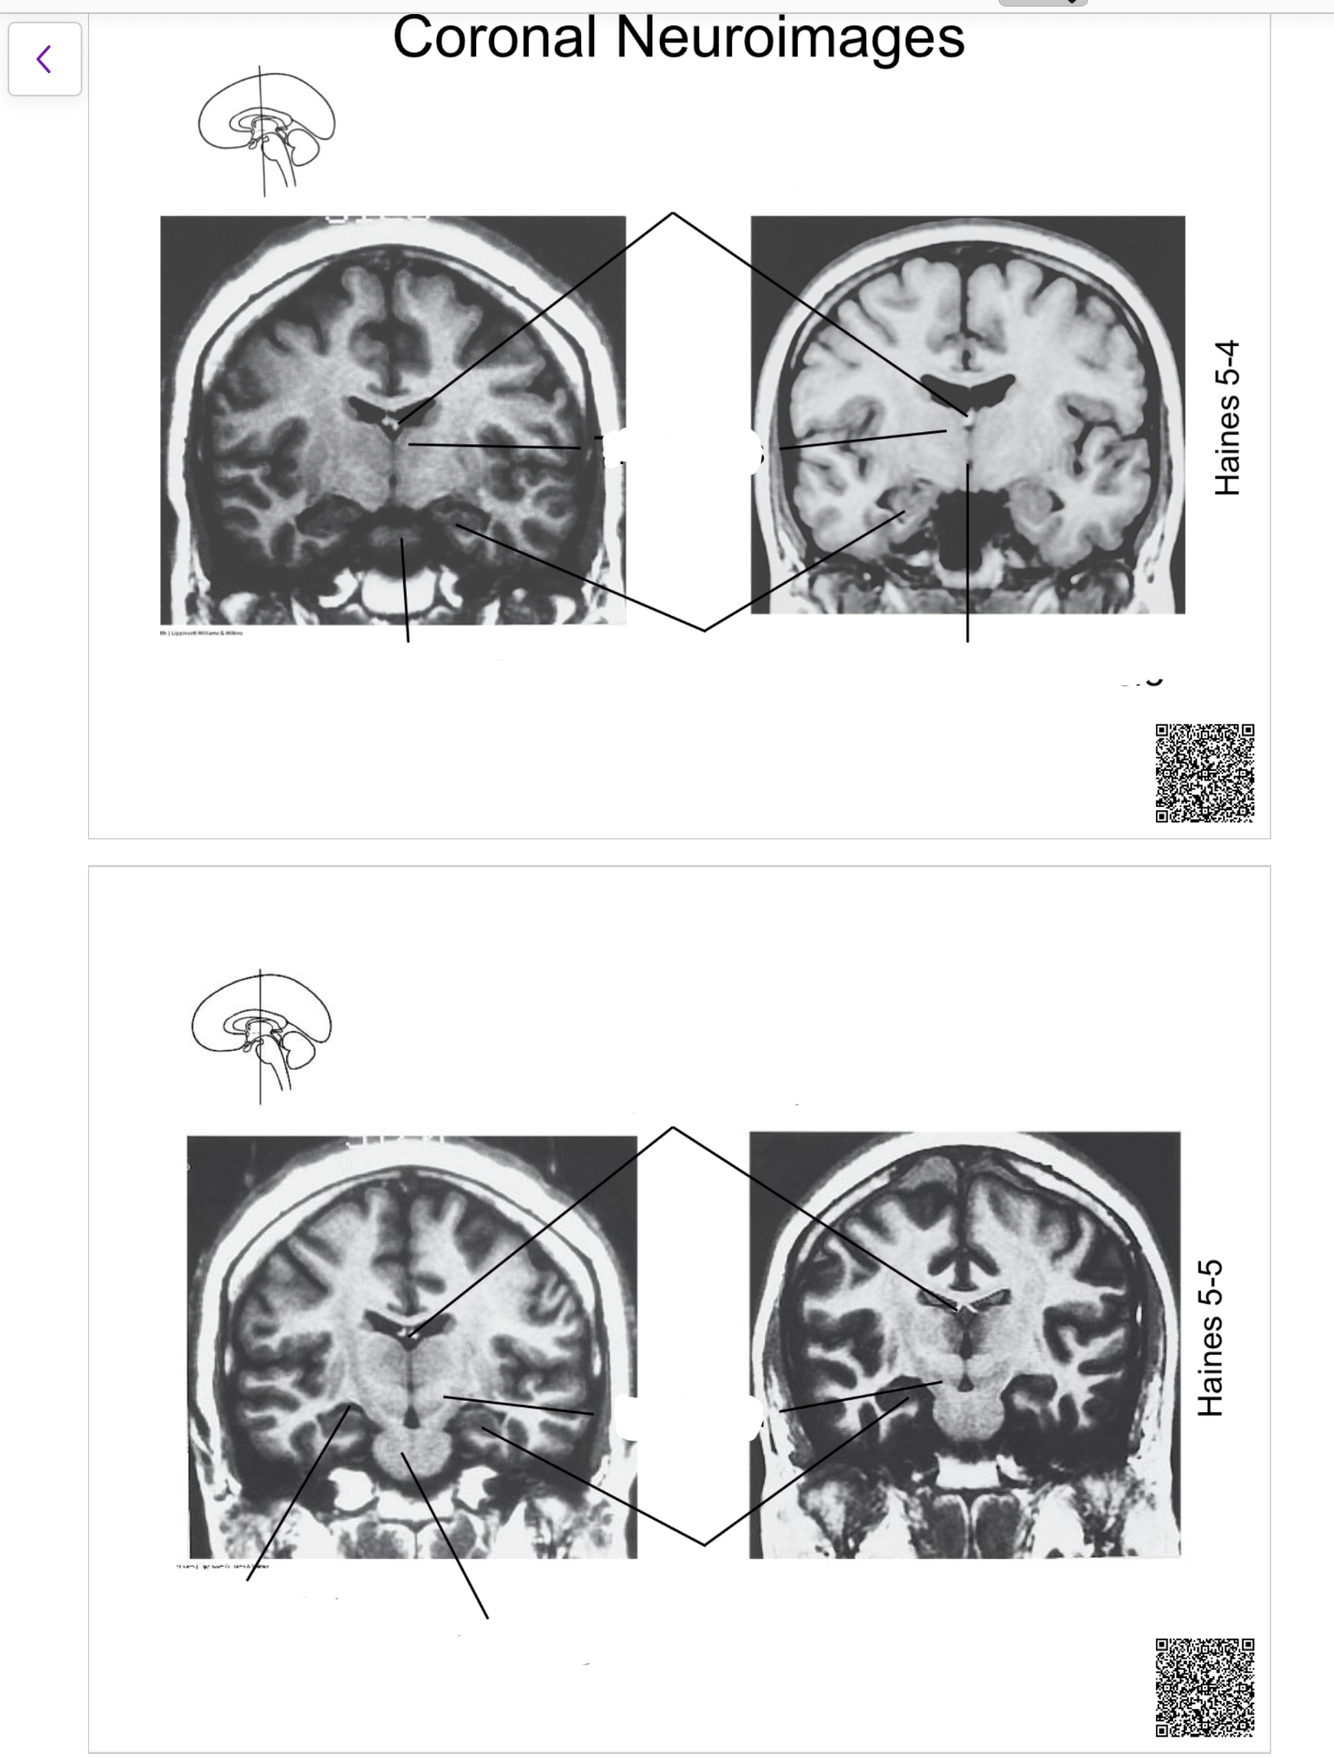

The structure indicated by the red line is?

other format too much work….